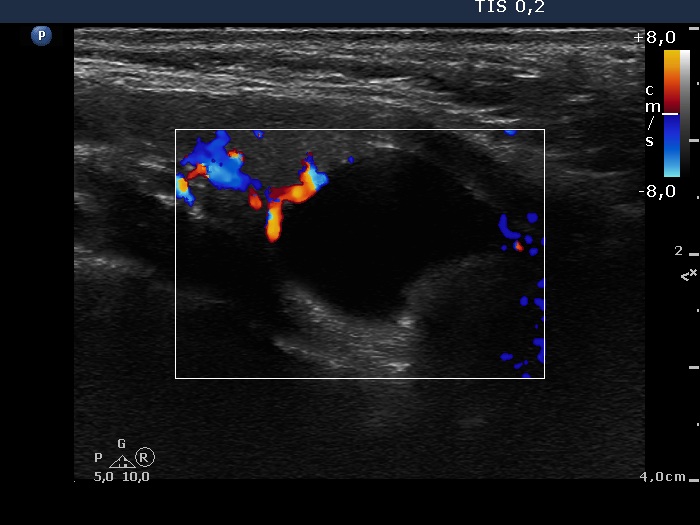

Second examination 2 years later (2nd row of images)

Clinical presentation. The patient had no complaints.

Palpation: no abnormality.

Ultrasonography. The pattern was essentially the same. The cyst has recurred.

1.8 mL watery fluid was aspirated.

Suggestion: ultrasound examination every second year.

Comment. The watery color of the cystic fluid is very specific for parathyroid origin.